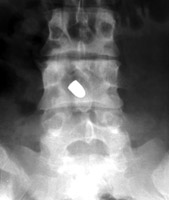

Two sets of frontal and lateral radiographs, separated only by time, which reveal the "tumbling bullet sign"--which is simply a bullet which changes its location and orientation within a solitary bone cyst. This sign serves two purposes. It is documentation of the evolution of a solitary bone cyst as a corollary of trauma, and reveals the free movement of the foreign body within the confines of the lesion establishing its cystic rather than solid nature. It is similar to the fallen fragment sign.

- Click on the image for a larger versionA - Click on the image for a larger versionB - Click on the image for a larger versionC - Click on the image for a larger versionD